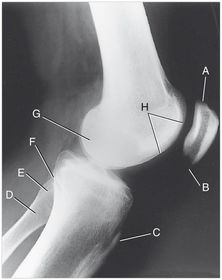

A. trochlear groove B. lateral epicondyle C. lateral condyle D. intercondylar fossa E. medial condyle F. medial epicondyle G. patellofemoral joint